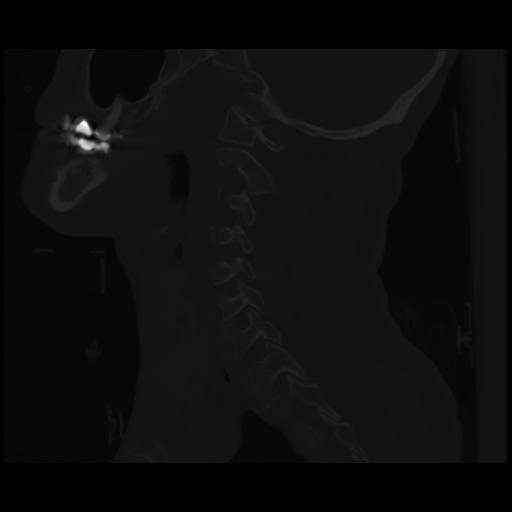

14 P.BLANDAS,,Sagittal,2.000,P.BLANDAS,Sagittal,